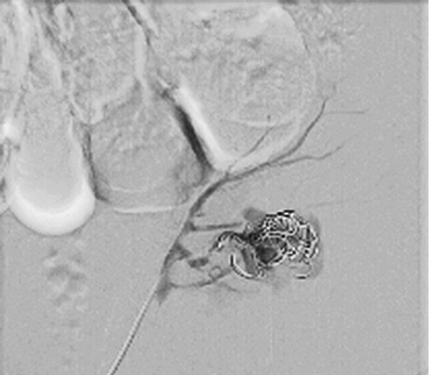

Cause of hematuria had to be determined, therefore urgent contrast enhanced computed tomography was performed (Figure 2) – contrast extravazation was found on the lower third of the right kidney (area of surgery), along with subcapsular hemathoma. Right hydroureteronephrosis and fluid in pelvis were observed. Blood clots and a small amount of contrast in the bladder were seen.

Figure 2. Contrast extravazation was found on the lower third of the right kidney (white arrow), subcapsular hemathoma (grey arrow)